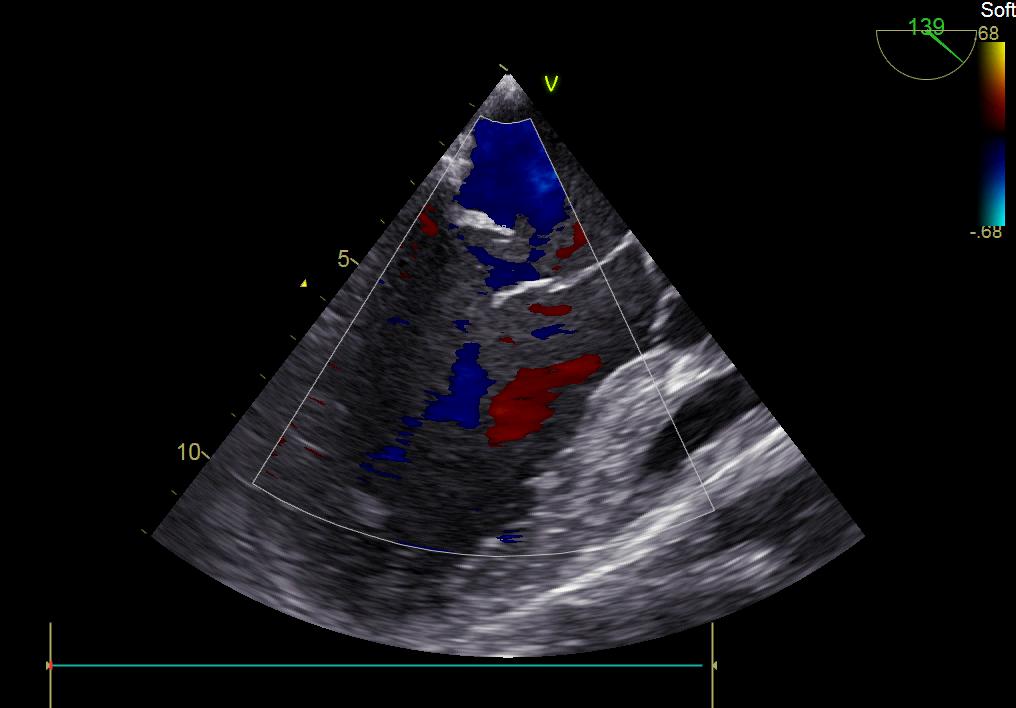

患者何某,42歲男性,因心功能不全入住我院心胸外科,心臟彩超提示二尖瓣后葉脫垂伴有重度返流及心臟擴(kuò)大,在迅速糾正心衰后,手術(shù)便提上日程,心胸外科廖金文主任多次組織全科及兄弟科室討論,在二尖瓣置換及成形術(shù)上,最終決定采取二尖瓣成形術(shù)。為保證手術(shù)安全,討論圍手術(shù)期各個細(xì)節(jié),所謂細(xì)節(jié)決定成敗,因為術(shù)前的細(xì)致全面,加上術(shù)中的一絲不茍及術(shù)后的精細(xì)化管理,患者術(shù)后恢復(fù)順利,健康出院,復(fù)查心臟彩超未見二尖瓣返流。

術(shù)前彩超